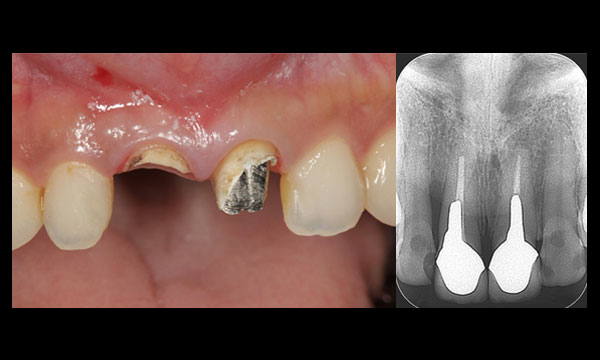

症例1

術前

前歯が根の途中から折れてしまいました。

術後

インプラントを使って、審美、機能回復しました。